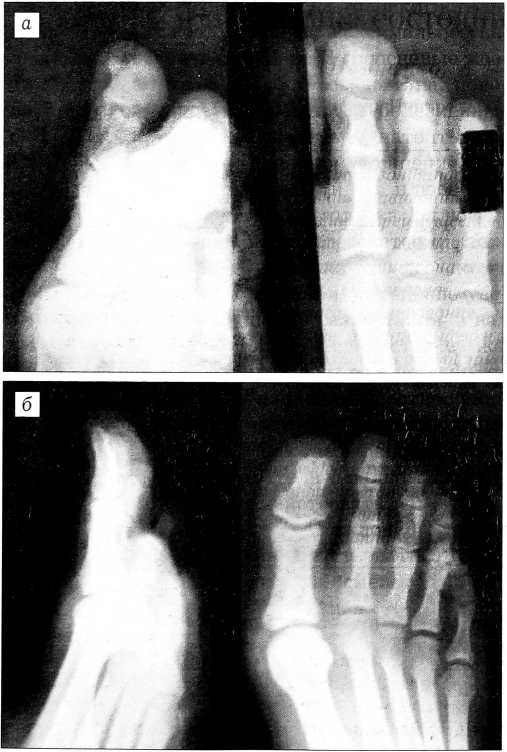

На рентгенограммах поврежденного пальца выявлено расширение суставной щели дистального межфалангового сустава и небольшое смещение дистальной фаланги к тылу (см. рисунок, а).

Закрытое вправление вывиха оказалось безуспешным. На 3-и сутки после травмы произведена операция — открытое вправление вывиха. Под местной анестезией 2% раствором новокаина (4 мл) по Лукашевичу—Оберсту дугообразным разрезом длиной 3 см на тыле пальца обнажено сухожильное растяжение. Последнее продольно рассечено, вскрыт дистальный межфаланговый сустав. Грубого смещения суставных поверхностей не определяется. Между суставными концами фаланг ущемлена фиброзная подошвенная пластинка толщиной 4 мм. С помощью микропинцета пластинка «вытолкнута» в подошвенную сторону. Суставные поверхности фаланг приблизились друг к другу. Тотчас исчез симптом «старой пружины». Рана послойно ушита наглухо. Наложена гипсовая шина. На контрольных рентгенограммах соотношения в суставе правильные (см. рисунок, б).

Рентгенограммы переднего отдела стопы больного Г. до операции (а) и после операции (б).